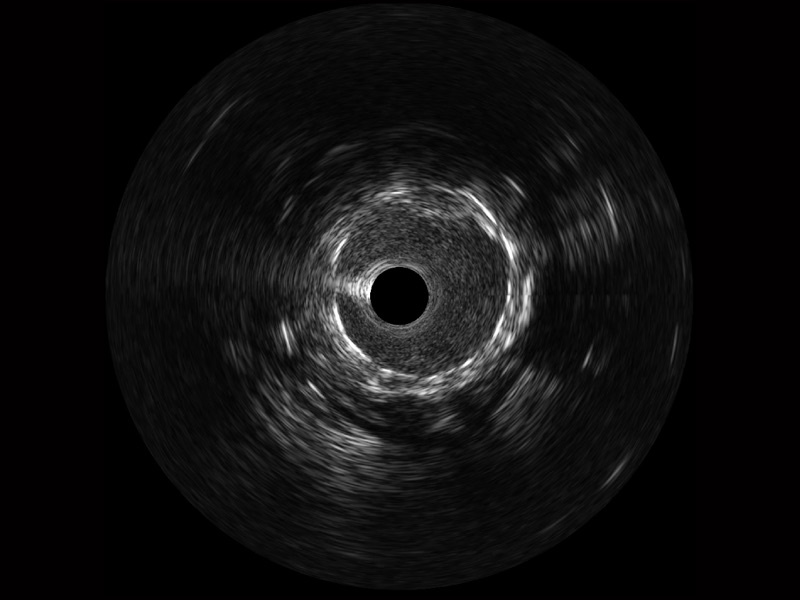

乐玩lewin国际宽频IVUS图像

传统IVUS图像

对比传统IVUS导管成像,乐玩lewin国际宽频IVUS图像的近场支架梁显影更细腻,远场中膜外血管仍清晰可辨,兼顾远中近,兼顾分辨力与穿透深度